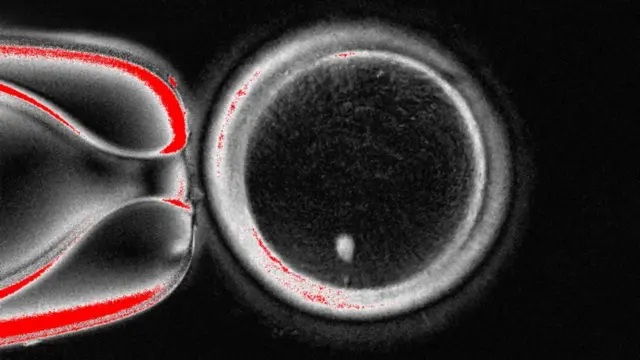

รายงานการศึกษาฉบับนี้ซึ่งถูกตีพิมพ์ในวารสารเนเจอร์ คอมมูนิเคชันส์ (Nature Communications)แสดงให้เห็นการสร้างไข่ที่มีศักยภาพในการผลิตตัวอ่อน 82 ใบ ซึ่งทั้งหมดถูกผสมด้วยอสุจิแล้ว และไข่บางใบก็พัฒนาไปถึงระยะแรกของการพัฒนาตัวอ่อน ทว่ายังไม่มีไข่ใบใดที่พัฒนามาเกินกว่าระยะเวลา 6 วัน

แต่เทคนิคนี้ยังไม่สมบูรณ์มากนัก เพราะไข่ยังเลือกทิ้งโครโมโซมแบบสุ่ม ซึ่งจำเป็นจะต้องเหลือโครโมโซมทั้ง 23 ชนิดไว้อย่างละหนึ่งเพื่อป้องกันโรค แต่สุดท้ายแล้วกลายเป็นว่ามักจะมีโครโมโซมบางชนิดซ้ำกัน 2 ชุด ขณะที่บางชนิดก็สละทิ้งไปจนไม่เหลือเลย

นอกจากนี้อัตราการประสบความสำเร็จยังมีน้อยอยู่ที่ราว 9% และโครโมโซมต่างๆ ก็พลาดกระบวนการสำคัญที่เรียกว่าการไขว้เปลี่ยน (crossing over) ซึ่งคือการจัดเรียงดีเอ็นเอใหม่